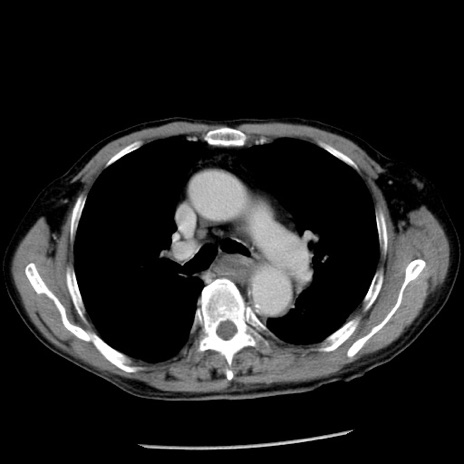

症例26(横断像)

【症例】80歳代男性

【主訴】嘔吐

【現病歴】昨晩2回嘔吐あり、今朝になっても嘔吐あり。来院。

【既往歴】胃潰瘍

【身体所見】意識清明、BT 37.6℃、BP 166/95mmHg、HR 100bpm、SpO2 97%、腹部:平坦・軟、腸蠕動音聴取良好、圧痛なし。

【データ】WBC 21900、CRP 1.46